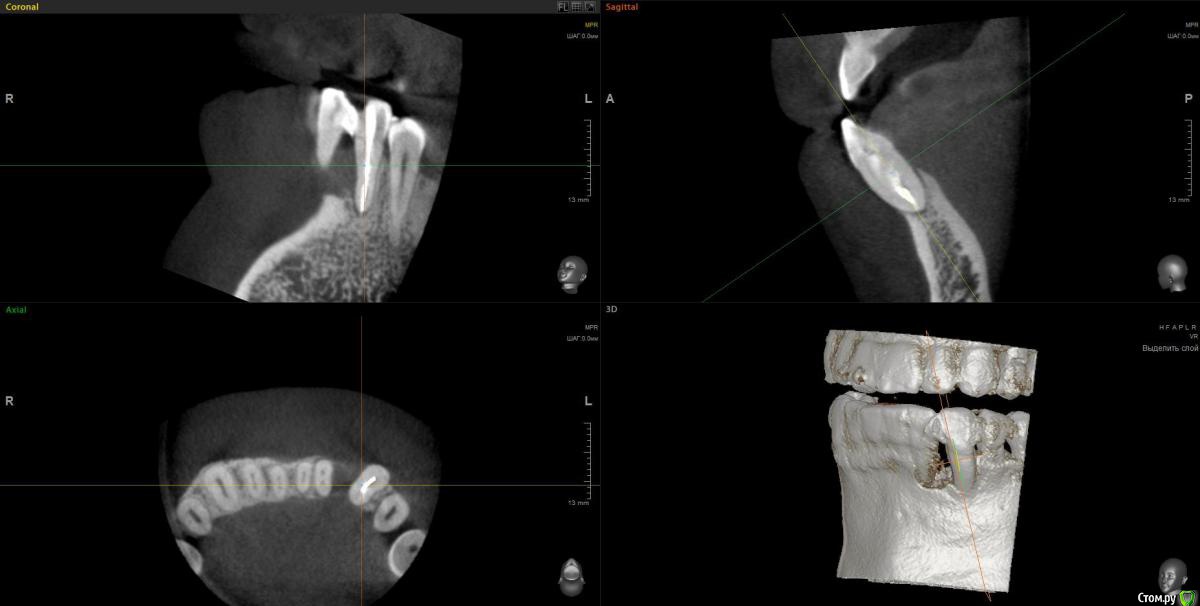

wladdX Опубликовано 3 февраля, 2017 Поделиться Опубликовано 3 февраля, 2017 Пациент 37 лет. 2,5 года назад в другом лечебном учреждении оперировали, по представленной ксерокопии карты, пародонтальную кисту. Прежних Rg-грамм нет.Сейчас следующая картина: Зубы 32 и 33 удаляем, а как далее правильно поступить?Каким способом лучше возместить дефект кости? Ваше мнение, коллеги? Ссылка на комментарий

wladdX Опубликовано 6 февраля, 2017 Автор Поделиться Опубликовано 6 февраля, 2017 Боюсь, что ничего из предложенного выше не выйдет. Вестибулярная и язычная стенки альвеол отсутствуют почти полностью. Зубы подвижны, почти постоянное гноетечение из карманов. Ссылка на комментарий

wladdX Опубликовано 6 февраля, 2017 Автор Поделиться Опубликовано 6 февраля, 2017 (изменено) Тоже склоняюсь либо к сетке либо к "sausage".Плохо, что есть гноетечение, из-за этого опасаюсь делать сразу после удаления. Изменено 6 февраля, 2017 пользователем wladdX Ссылка на комментарий